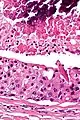

Intermed. mag. Very high mag.

Very high mag.